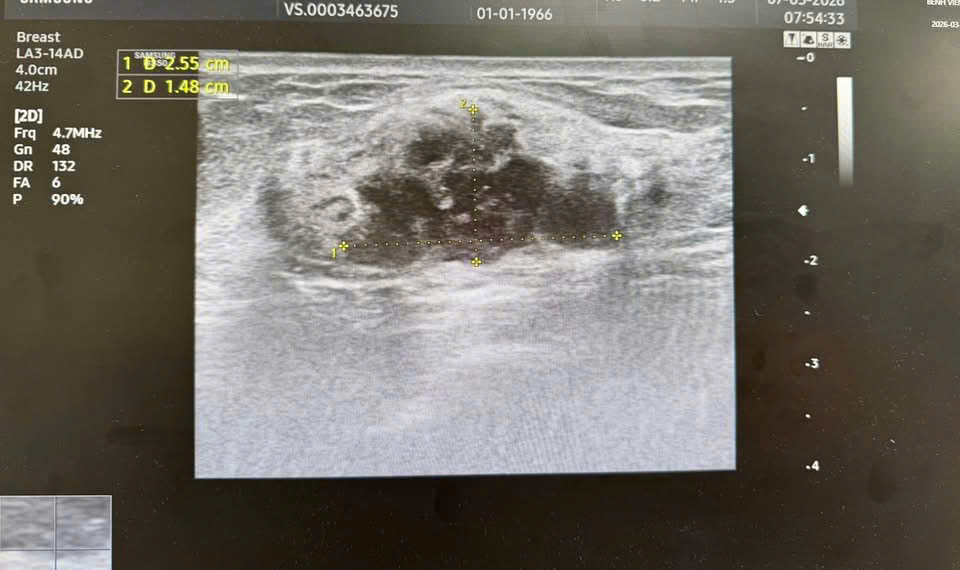

Kết quả siêu âm và chụp X-quang tuyến vú cho thấy hình ảnh khối u được phân loại BIRADS 4 – nhóm nghi ngờ ác tính cần làm thêm xét nghiệm. Sau đó, kết quả xét nghiệm tế bào học xác định bệnh nhân mắc ung thư biểu mô tuyến vú giai đoạn sớm.